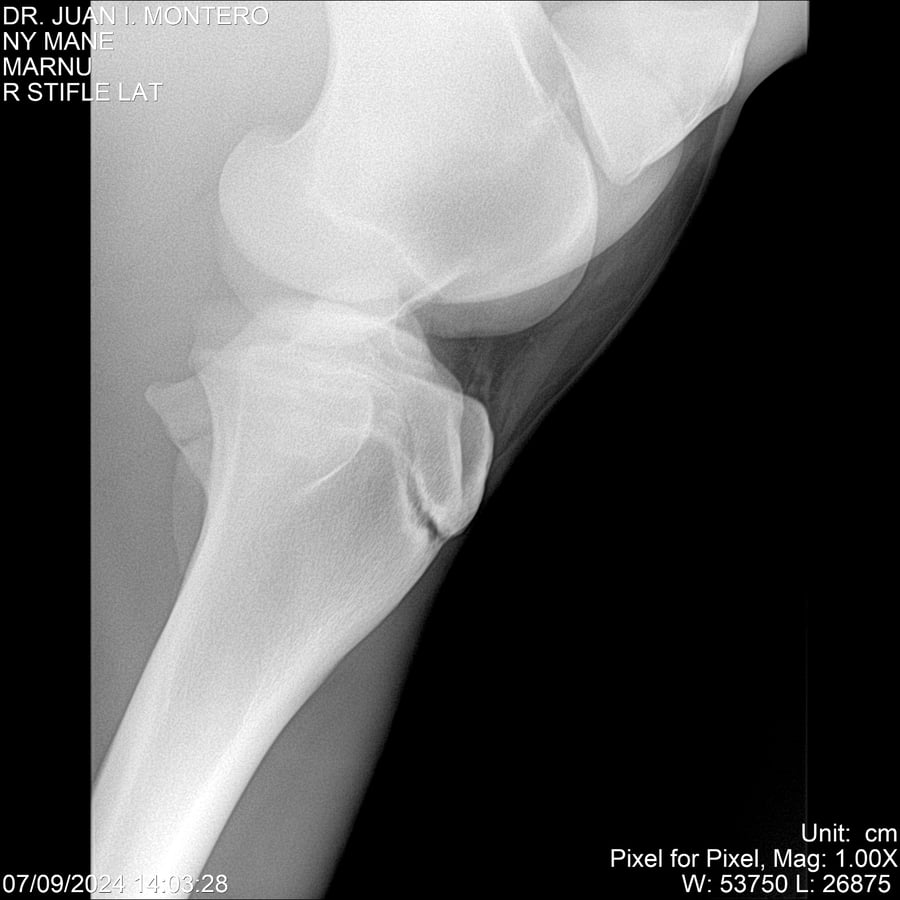

LOTE 20, NY MANE Lote Anterior Volver al remate Lote Siguiente Ficha Contacto Montevideo - Ficha del Lote Identificador: #282520 Categoría: Yeguarizos 76 Visualizaciones ClicData Contacto Empresa: Abelenda N. R., Walter Hugo Nombre*: Teléfono* : E-mail* : Mensaje Enviar Registrese gratis Este contenido Exclusivo está disponible sólo para usuarios registrados Ingresar